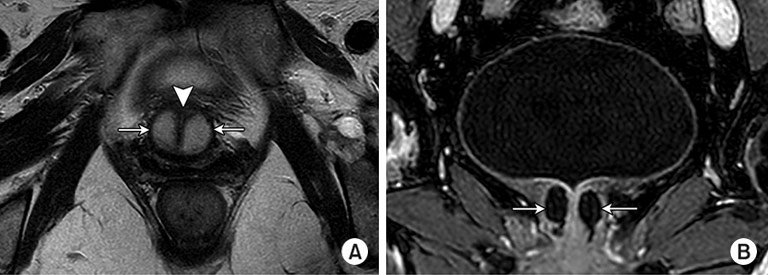

Gemeinsam mit dem Prof. Stehling Institut für Bildgebende Diagnostik haben wir spezielle bildgebende Verfahren entwickelt, um die kritischen anatomischen Strukturen am Beckenboden sichtbar zu machen, darunter die dynamische Darstellung des Beckenbodens unter Belastung und die hochauflösende Darstellung des Harnröhrenschließmuskels.

Dadurch können wir die Behandlung mit Stammzellprodukten genau auf den Bereich ausrichten, in dem die Stammzellen am meisten benötigt werden. Mit dem Stammzellsekretom können wir den Harnschließmuskel perfundieren, um seine Funktion zu reaktivieren, ohne die empfindliche anatomische Struktur des Schließmuskels zu beschädigen. Dies ist einer der vielen Vorteile gegenüber chirurgischen Eingriffen, die unweigerlich zu einer teilweisen oder vollständigen Zerstörung des Schließmuskels führen.

Lokale Injektionen von mesenchymalen, muskulären und fetthaltigen Stammzellen haben in Tiermodellen mit mechanischen, nervalen oder äußeren Verletzungen des Harnröhrenschließmuskels bei Belastungsharninkontinenz zu erfolgreichen Ergebnissen geführt. Erste klinische Versuche mit Stammzellen zur Behandlung der Belastungsharninkontinenz bei männlichen und weiblichen Patienten haben vielversprechende funktionelle Ergebnisse mit minimalen unerwünschten Wirkungen erbrachtV.

Während die Injektion von Füllstoffen die Harninkontinenz verbessern kann, insbesondere bei Frauen VI (siehe unten), kann die Injektion von Stammzellen in und unmittelbar neben die Harnröhre bessere funktionelle Ergebnisse liefern.